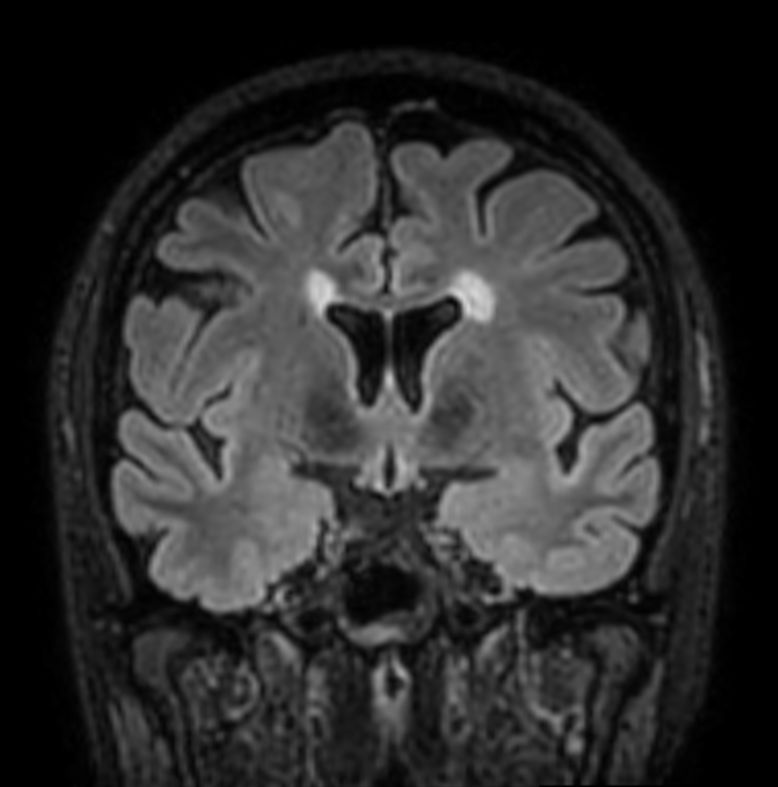

3D T2w FLAIR BrainVIEW Compressed SENSE

3D T2w FLAIR BrainVIEW (reformat) Compressed SENSE